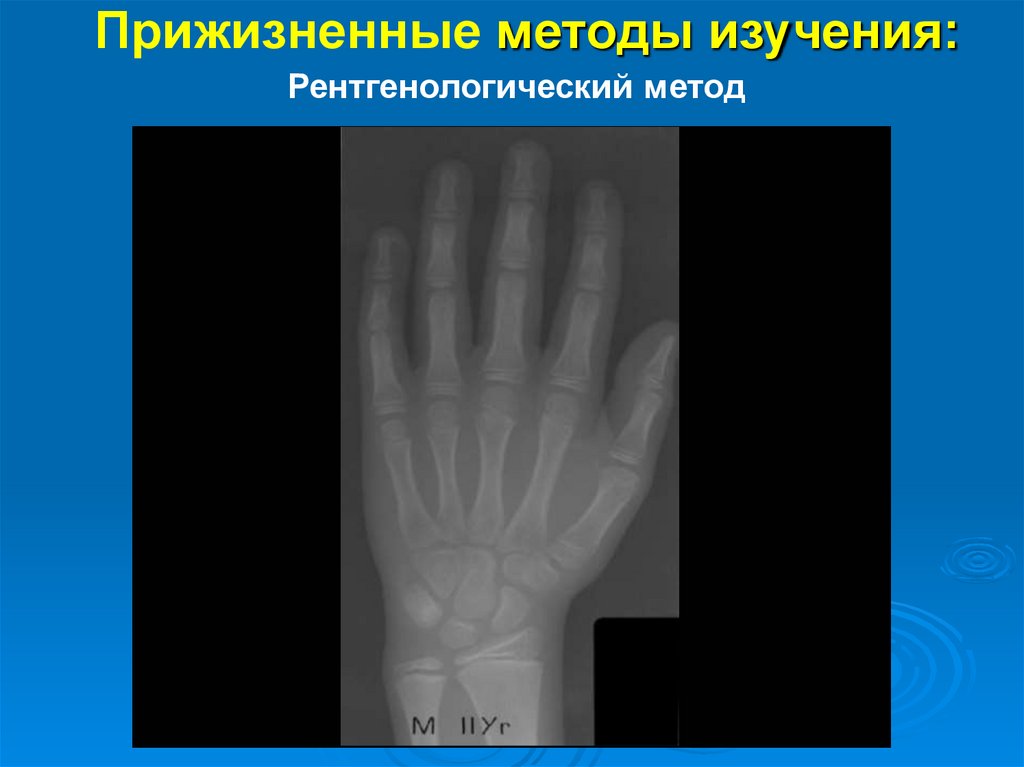

Прижизненные методы изучения:

Рентгенологический метод